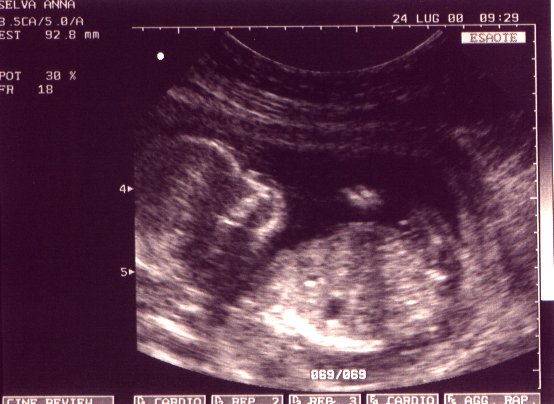

Settimana dopo settimana il bambino si sviluppa dentro la mamma protetto dalla placenta che lo avvolge e nutrito attraverso il cordone ombelicale. Visite ginecologiche programmate vi permetteranno di vederne la crescita. Grazie all’ecografia si possono misurare le dimensioni e dare anche una stima del peso. Più il bambino diventa grande più le parti del corpo diventano riconoscibili.